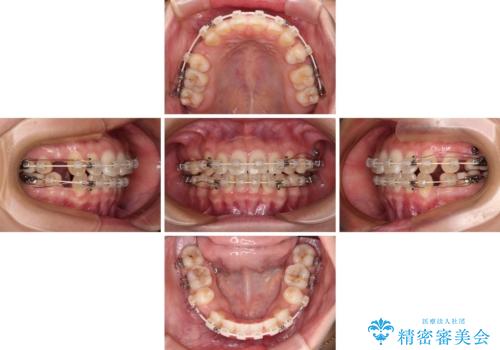

- 口元の突出感と上下前歯のズレを気にして来院された患者様です。

舌の突出癖により上下の前歯は非接触となっている状態でした。

舌のトレーニングを行わないと上下前歯の接触達成は困難であるため、トレーニングをしっかりと行っていただきながら、治療を進めて行くこととしました。

突出感改善のため、上下左右の第一小臼歯4本を抜歯し、ワイヤー装置にて矯正治療を行うこととしました。